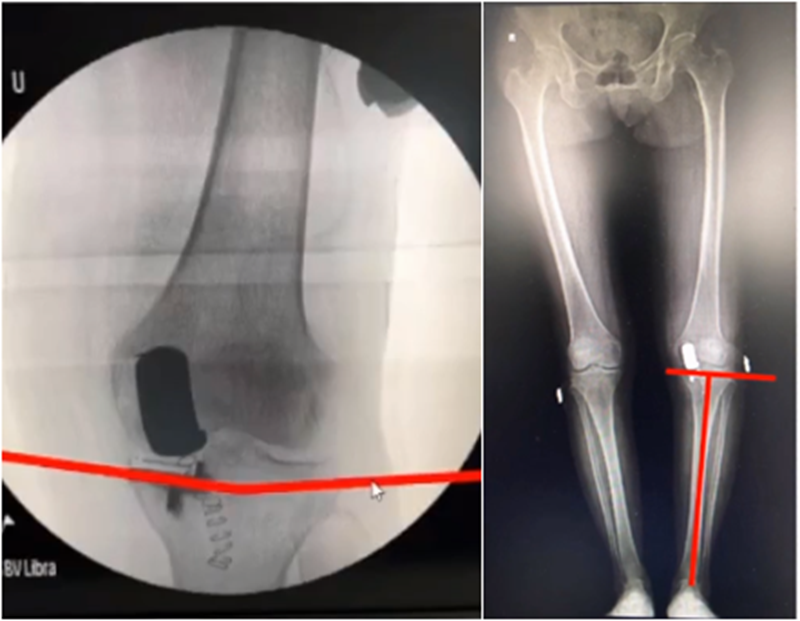

五、关于力线与假体位置——是否要求全长片?

牛津单髁课程表明,单髁只纠正关节内畸形,恢复下肢得病前的力线,不纠正关节外畸形。

但实际术后需要通过全长片来判断是否能取得好的力线,判断有无过度矫正或矫正不足的情况出现。还需要通过全长片区分内翻畸形的来源在哪里,是否能矫正,对适应证的选择有一定帮助。如果术后下肢整体力线外翻3°,则说明外侧间室压力明显升高。

小结:对于下肢整体力线,首先保证术后力线不能外翻,术后力线内翻不能超过10°,而术前关节外畸形不能超过10°。

除了下肢整体力线,还要考虑假体位置。理想状态下,假体位置对位好,力线轻度内翻。

牛津单髁在假体评判中,提到股骨内外翻有10°容忍度,胫骨内外翻有5°,股骨屈伸在0-15°之间,胫骨后倾在 7-(﹣5)后倾之间。但评判标准中没有提到此种方式是基于全长片还是局部片。

文献中建议假体内外翻不大于4°,如果假体出现外翻,后倾大,会造成内侧皮质压力异常增高,增加内髁骨折风险。如果假体内翻超过5°,增加胫骨平台松动风险。

但有时候力线好,假体和外侧关节线会成角,那么对于此种情况,应如何判断假体位置内外翻定义?和外侧关节线比较,属于外翻假体;和下肢机械轴比较,属于中立位假体。

小结:判断股骨胫骨假体位置,是基于局部X线的判断,是考虑行走时关节线的方向为基准,此时内外翻不能超过5°,而不能从全长片来判断。